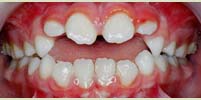

מנשך הפוך

ליקוי האופייני לילדים בעלי מבנה גנטי מולד של לסת צרה או בעיה התפתחותית הנובעת כתוצאה מתת התפתחות של הלסת העליונה עקב נשימת פה וחסימת דרכי הנשימה באף.